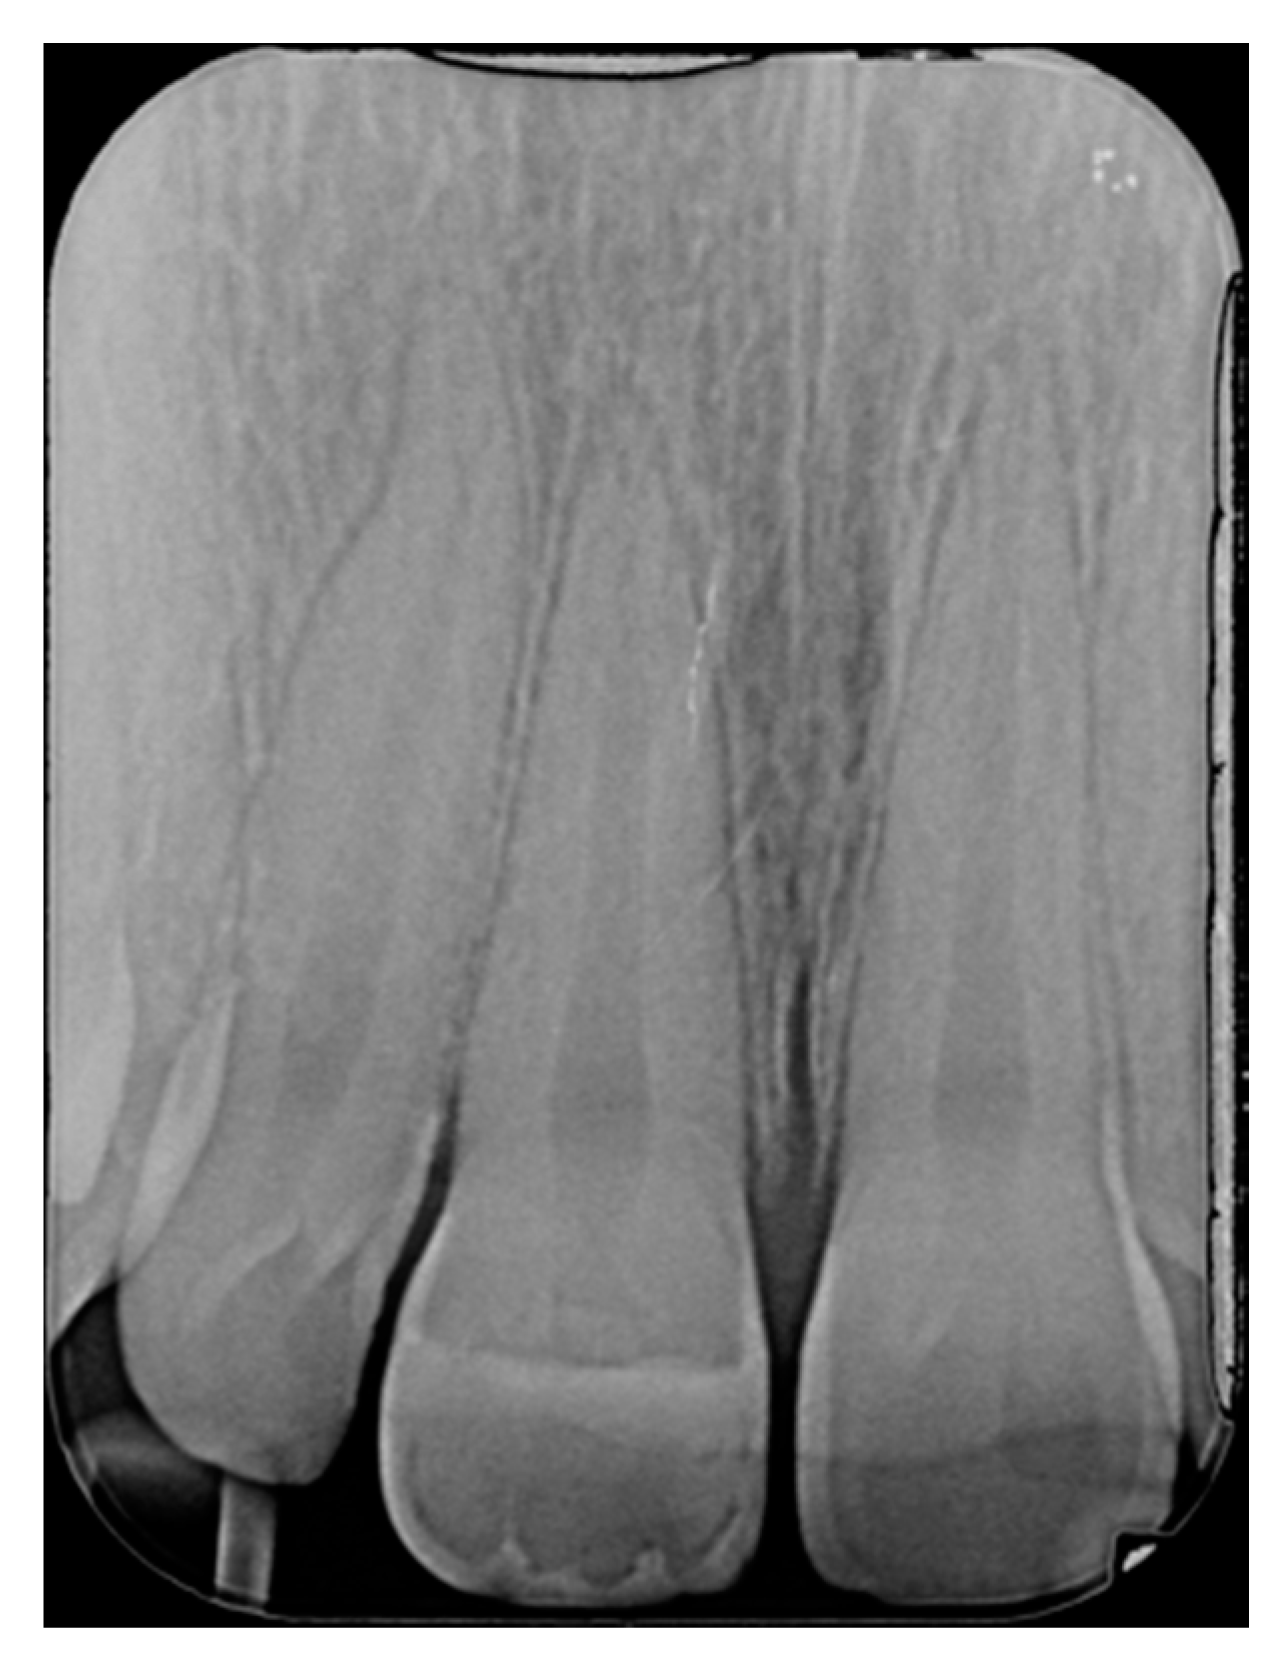

Figure 17.

One year post-operative x-ray. Reprinted from Restauri diretti nei settori anteriori, G. Paolone, S. Scolavino, © 2021, with permission from Quintessence Publishing Italy.

Figure 18.

Five years post-operative.

Figure 19.

Five years post-operative x-ray.